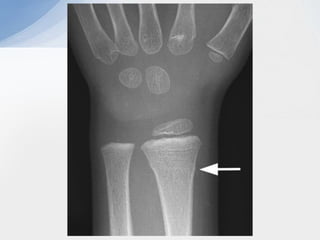

Galleazzi

• #6 Torus fracture